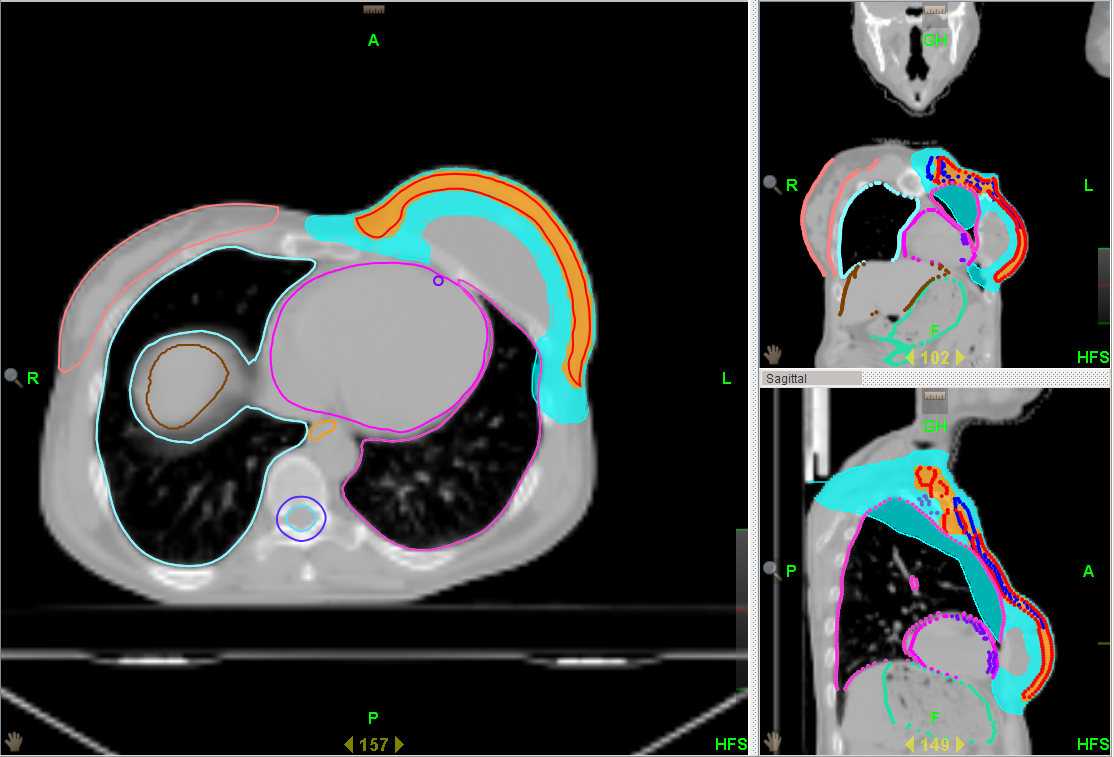

Al fine di ridurre intensità e frequenza degli effetti collaterali dovuti al trattamento radioterapico in seguito ad una ricostruzione mammaria, viene utilizzata la tecnica HALFMOON (semiluna), che consente di modulare l’irradiazione sulla mammella ricostruita dopo una mastectomia e risparmia protesi/espansore, garantendo la stessa efficacia terapeutica delle tecniche tradizionali (fig. 1).

| Fig. 1 | Fig. 2 |